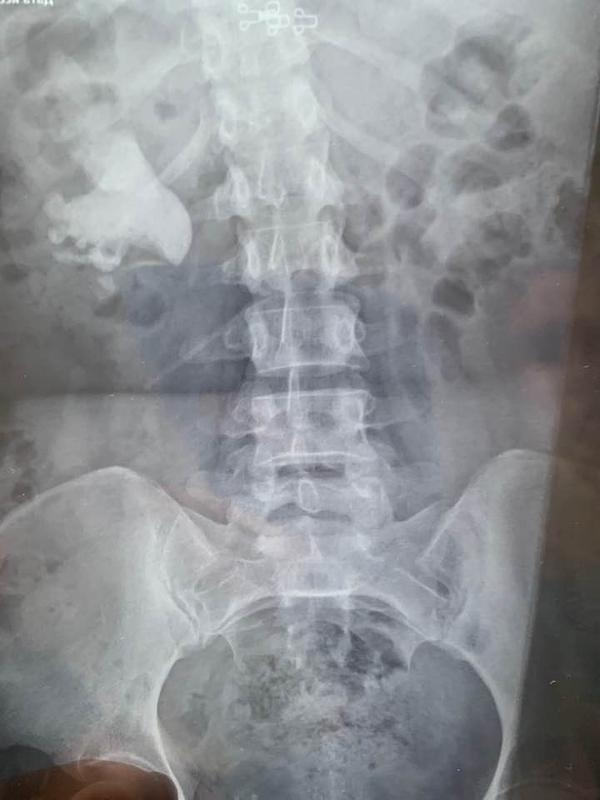

В зависимости от локализации камня, его структуры и размера командой специалистов принимается решение о методике его удаления. Самыми "тяжелыми" случаями являются так называемые коралловидные камни. Раньше они удалялись только с помощью открытой операции, после которой пациент был вынужден находиться в стационаре до двух недель.

"В арсенале нашего отделения есть самое современное оборудование (электронно-оптический преобразователь, лазерный литотриптор, фиброуретерореноскоп), которое позволяет малоинвазивно, через естественные пути или через минимальные до 5 мм проколы проводить сложнейшие операции, – рассказывает Александр Унгурян, заведующий отделением урологии городской больницы экстренной и скорой медицинской помощи, врач-уролог высшей категории, член Европейской, Американской и Украинской ассоциаций урологов. – Сейчас в случае коралловидных конкрементов мы применяем так называемую перкутанную хирургию – через прокол в области спины мы вводим в почку крошечную камеру и зонд, разрушаем камень лазером и тут же убираем его осколки. После такой операции пациент выписывается всего через 3-4 дня. Ему назначают минимум медикаментов, и он активен в тот же день".